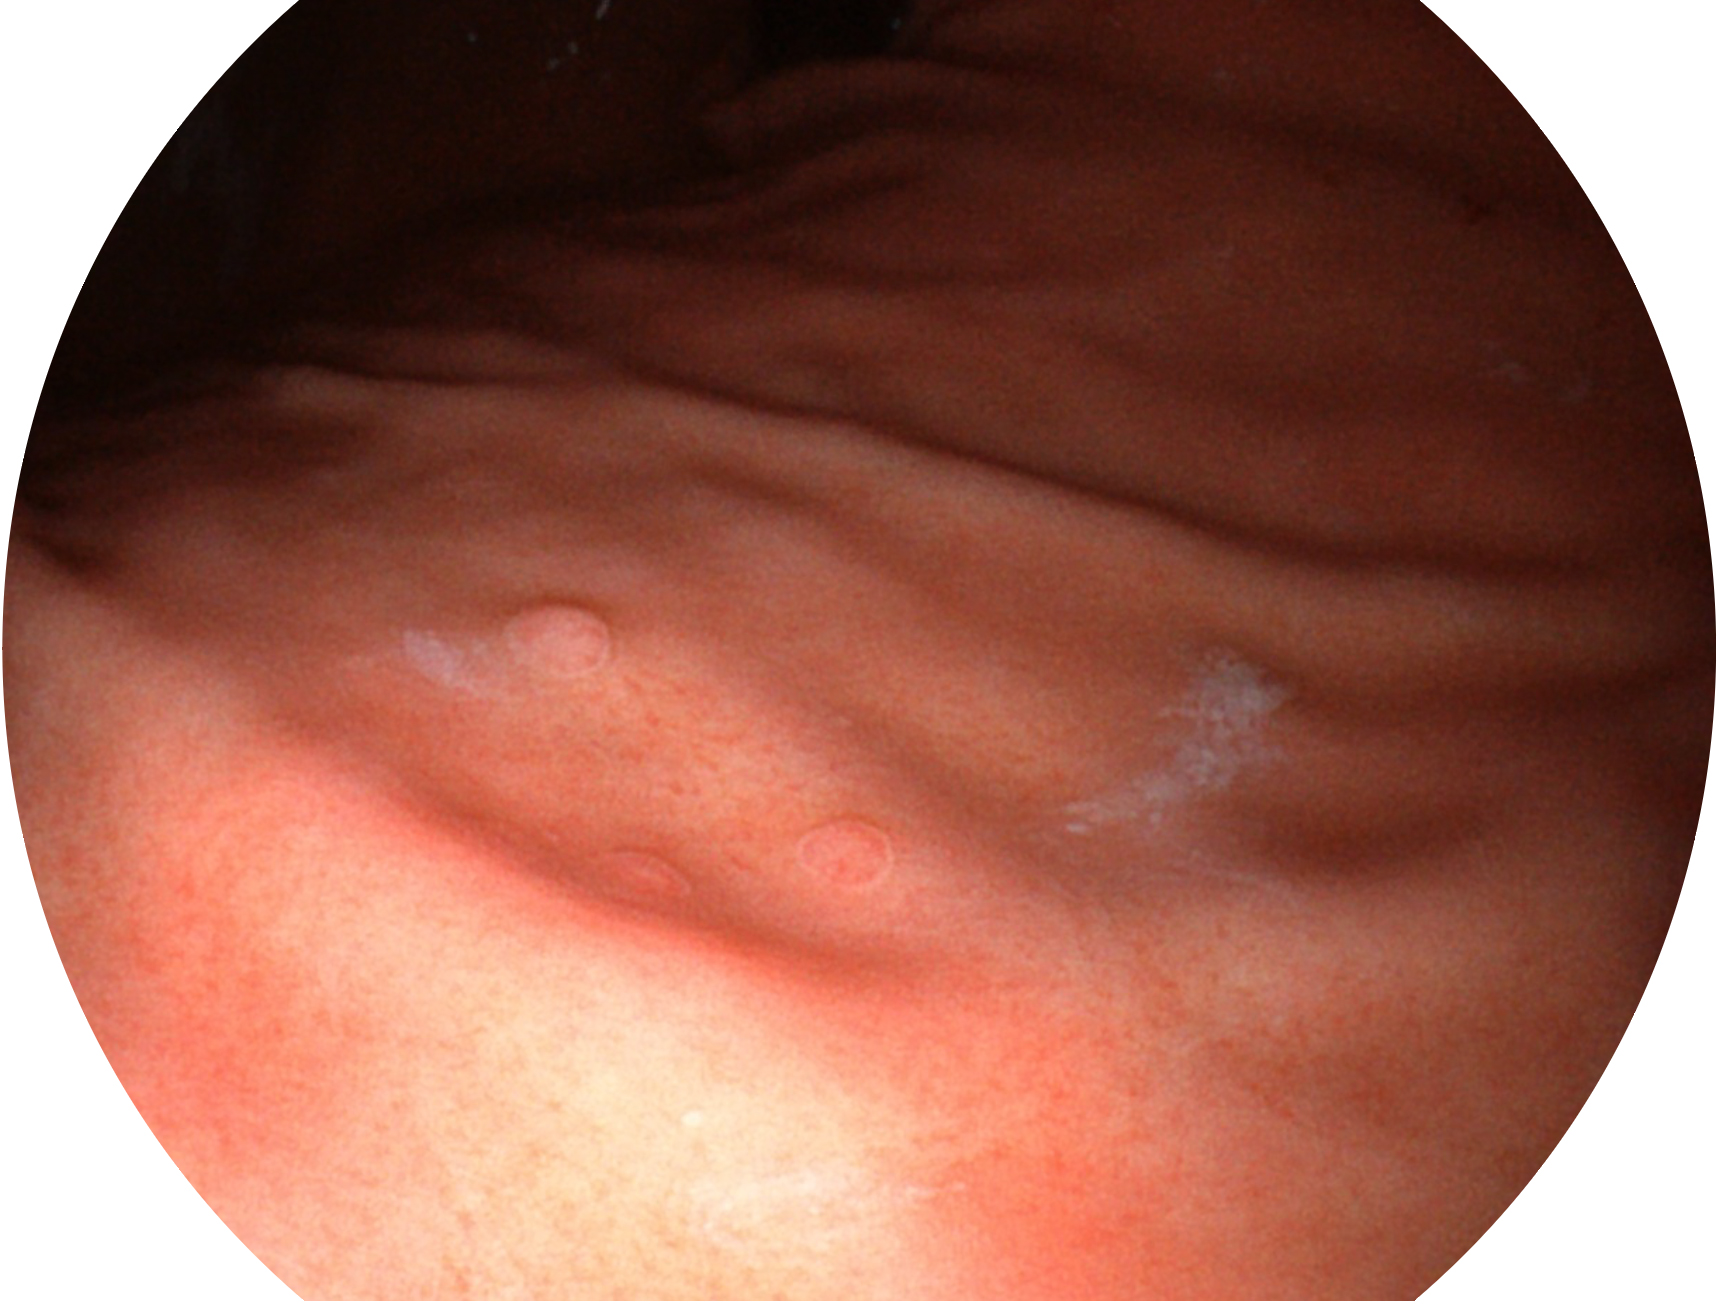

狗万官方网站新开发的内镜染色技术,主要是基于多波长LED 光源的开发,VLS-55Q 四波长LED 光源是由四个不同颜色的LED光按照相应照明模式所规定的特定发光比例进行合束后形成,合束后形成的照明光的光谱由红光、绿光、蓝光及蓝紫光这四个不同的波段范围构成。具有更高光谱自由度,通过光谱比例的控制,实现了聚谱成像技术,英文全称为“Spectral Focused Imaging, SFI”,缩写为“SFI”和光电复合染色成像技术,英文全称为“Versatile Intelligent Staining Technology, VIST”,缩写为“VIST”。